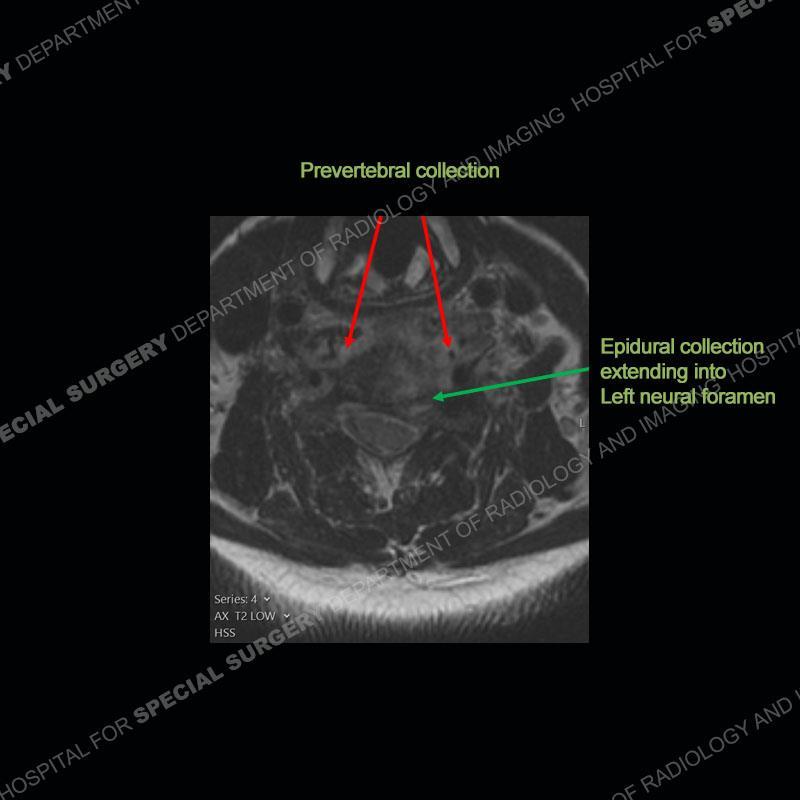

The radiographs demonstrate a prevertebral soft tissue fullness centered at C5-C6 that persists even on extension. There is a slight loss of disc height at C5-C6. The CT more readily shows the prevertebral soft tissue swelling at C5C6 where there is a punctate focus of gas. On the MRI, there is a marked amount of edema and a heterogeneous collection in the prevertebral soft tissue at C5-C6. Edema is present of the C5 and C6 vertebral bodies with a loss of the normal architecture about the disc space. A heterogeneous epidural collection has formed that causes compression of the spinal cord asymmetric to the left side and also precipitates severe left sided neural foraminal stenosis.

Diagnosis: Spontaneous Retropharyngeal Abscess (RPA) with Discitis/Osteomyelitis, Epidural Abscess, and Cord Compression

Spontaneous RPA in the non-immunocompromised, adult population is an extremely rare occurrence. RPA most frequently occurs in young children and most typically after a URI. It may be associated with torticollis in Grisel syndrome. In the adult population, the pathomechanism is not well understood with some suggesting a hematogenous spread or perhaps a seeding from the adjacent aerodigestive tract. The abscess as in this case can extend to involve the vertebral column and then the neural elements. At times, this process can be treated with antibiotic therapy alone but when there are neurologic symptoms and especially progression of neurologic symptoms, surgical intervention is warranted. In this case, given the extent of the process and the patient’s clinical situation, a corpectomy with fusion was performed in addition to antibiotics.